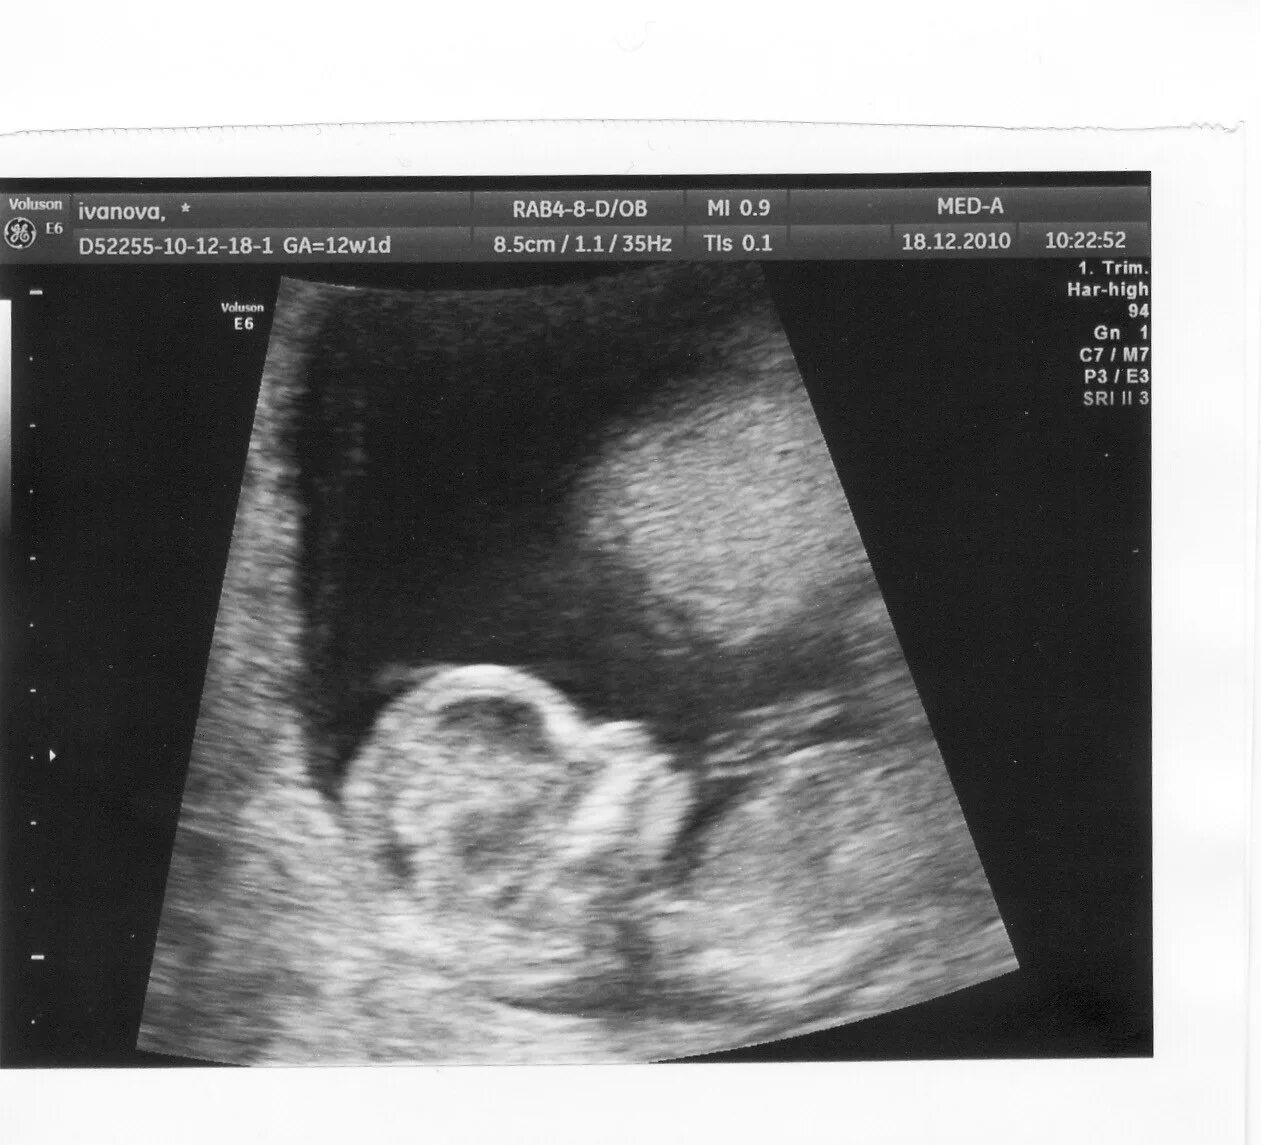

12 недель и два дня